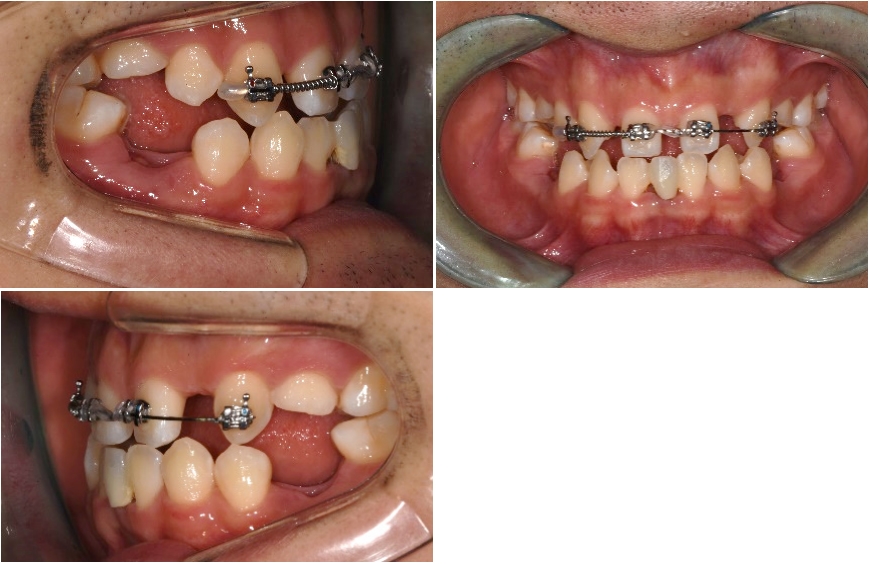

이 환자는 상악 양측 측절치와 양측 제1, 2 소구치, 하악 양측 제1, 2소구치, 양측 중절치의 결손을 가진 multiple congenital missing 환자입니다만 계속적 권유에도 불구하고 임플란트를 통한 전치부의 spacing 해결만을 원하였습니다.

때문에 상악에서만 부분교정을 통해 측절치 임플란트 식립 공간을 확보하기로 하였으며 동시에 상악 중절치의 반대교합 수정을 하기로 하였습니다.

양측 견치의 회전을 수정할 필요가 없고 중절치 이동을 위한 고정원으로 사용하기 위해 견치의 움직임을 최소화하였습니다.

견치 브라켓의 경우 원심쪽의 레진베이스를 두껍게 하여 견치 회전을 그대로 유지하기로 하였고 사전에 제작된 segmental archwire에 bracket slot이 평행하도록 setup하여 transferjig을 제작하였습니다.

중절치의 경우 양측 중절치가 근심으로 당겨지면서 치관의 mesial tipping이 예상되 므로 이를 상쇄해 주기 위해 bracket을 비뚤어지게 붙여서 중절치 치근이 서로 모아지는 방향이 되도록 배열하였습니다.

이어서 상악 양측 제1대구치에서 견치까지 설측에 resin wire splinting을 시행하여 견 치의 고정원을 강화하였습니다.